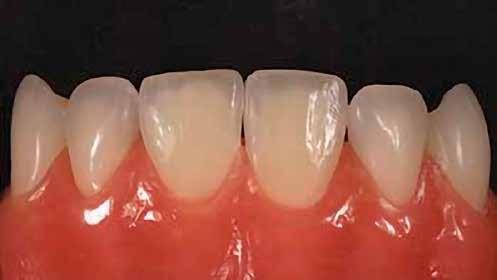

A posterior fogak direkt kompozit restaurációja az egyik leggyakrabban végzett beavatkozás a fogászatban. Az elmúlt években kiemelt figyelem irányult az elérhető eredmények optimalizálására, különös tekintettel a II. osztályú kavitás dobozának (Class II box) kialakítására, és a polimerizációs zsugorodásból eredő feszültség kezelésére. A téma körüli széles körű szakmai diskurzus ellenére van egy olyan lépés, amely gyakran nem kapja meg a kellő figyelmet: a mechanikai formázás protokollja. A mechanikai formázás alatt a restauráció kontúrjának kialakítását, a felesleges kompozit eltávolítását értjük a marginális szélekről, illetve ide tartozik a végső polírozás is. Ez a folyamat három fő lépésre bontható: a felszín oxigén által gátolt, nem polimerizált rétegének eltávolítása, a durva finírozás és a végső polírozás. Jelen publikációban részletesen bemutatjuk ezeket a lépéseket, valamint egy klinikailag hatékony megközelítést vázolunk fel a direkt posterior kompozit restaurációk befejezésére.

A végső polírozás célja egy sima, „zománcszerű” felszín kialakítása, amely a páciens lágyrészei számára komfortos, esztétikailag kedvező, valamint ellenáll a lerakódásoknak és az elszíneződésnek. Ez a folyamat négy fázisból áll.

Finom és szuperfinom, közepes méretű polírozó korongok alkalmazásával 10 000–15 000 fordulat/perc sebességen történik a restauráció peremének polírozása. A korongokat hátrafelé irányuló mozdulatokkal, 45°-os szögben kell vezetni a fog hossztengelyéhez képest.

Finom, gyémánttal impregnált szilikon polírozófejet használunk vízhűtéssel a restaurátum széleinek és a csücsök-lejtők polírozására. Ez a lépés fokozza a restauráció fényét, a karcolások már a durva finírozási szakaszban el lettek távolítva.

Kecskeszőr kefét (pl. Shiny S, https://optident. co.uk/product/shiny-s-goat-hair-brushes/) célszerű alkalmazni stabil nyomással, vízhűtés nélkül, a restaurátum barázdarendszerének polírozására. A polírkefe pumisz pasztával (pl. Vertex® Pumice Plus, https://www.dentaltotal.es/images/ marcas-dentaltotal/VERTEX/CATALOGO_VERTEX.pdf) használandó. Ez a lépés kiküszöböli a barázdákban maradó karcolásokat, amelyek középtávon hajlamosak elszíneződni.

A végső fényesség az 1 mikron szemcseméretű, alumínium-oxid alapú, vízbázisú polírozópasztával (pl. Enamelize®, Cosmedent; https://www.cosmedent.com/product-category/finishing-and-polishing/) érhető el, valamint filc polírozófejek és korongok segítségével. A polírozás fokozatosan

növekvő fordulatszámmal (3000–20 000 fordulat/perc) és csökkenő nyomással történik. A pasztát mindig a fogra/restaurációra kell felvinni, nem pedig a korongra, így elkerülhető a paszta szétszóródása a kezelőben. (Lásd a 10. és 11. ábrát.)

12. ábra: A premoláris fogak preoperatív állapota.

13. ábra: A premoláris fogak postoperatív fotója.

14. ábra: Egy moláris fog preoperatív állapota.

15. ábra: Egy moláris fog postoperatív fotója.